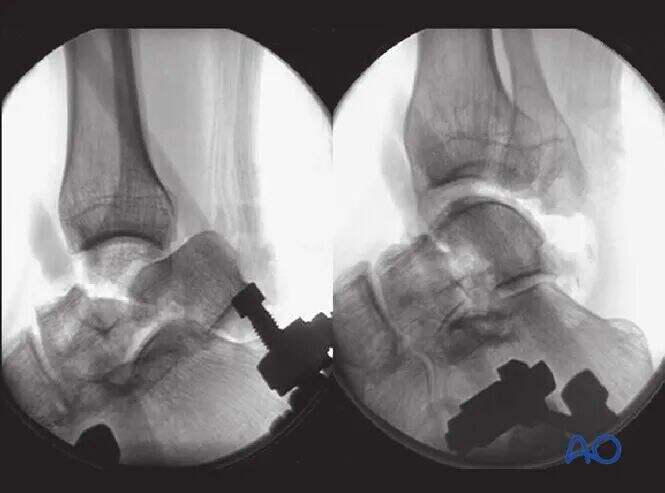

Ilustracija prikazuje pacienta pod splošno anestezijo z popolno mišično relaksacijo. Medialni distraktor se uporablja za doseganje redukcije frakture vratu talusa s pomočjo vleke, s čimer se odpravi rotacijska deformacija in se telo talusa vrne v anatomsko pozicijo.

Druga slika prikazuje učinek redukcije vratu talusa, pri čemer je tibiotalarni sklep v raztegnjenem položaju.